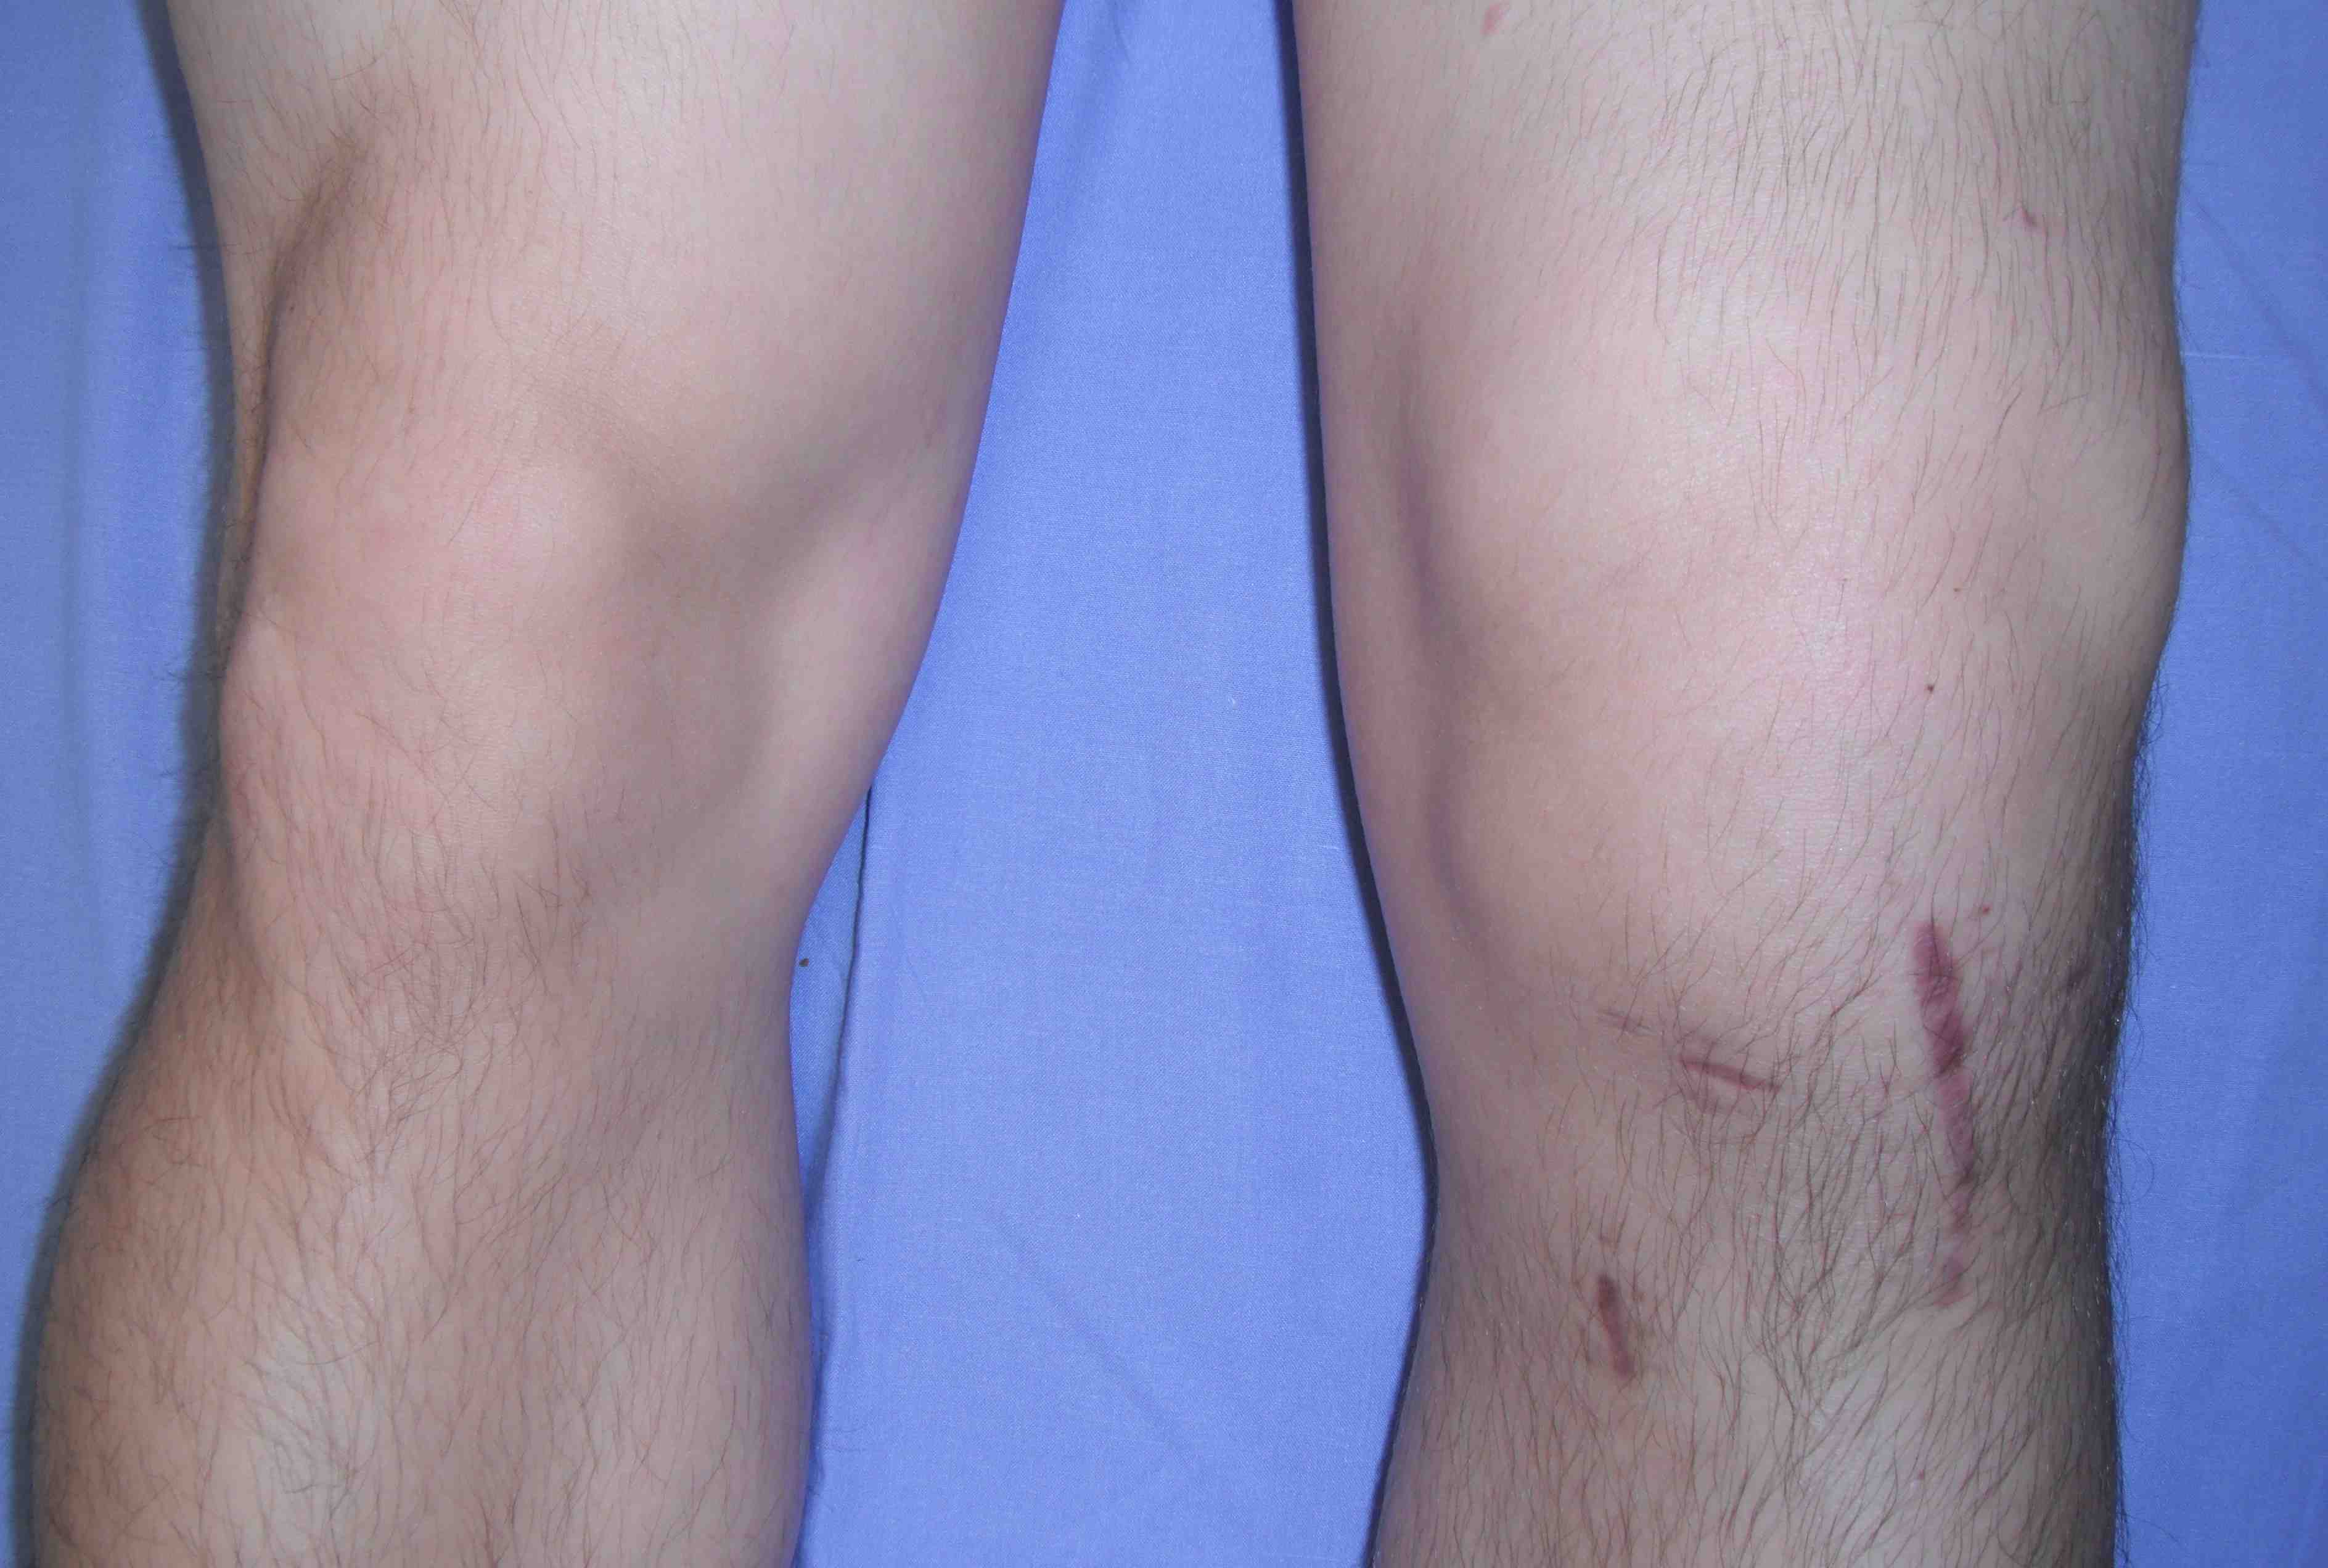

Incidence

Knee > Hip

- superficial position

- limited cover of well vascularised muscle

- watershed area of skin blood supply anterior to the skin incision

- much increased in fully constrained prosthesis

Ideal < 1%